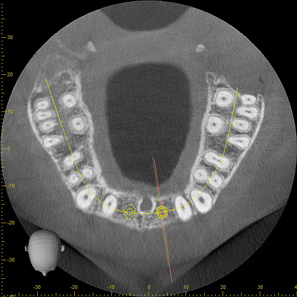

Fig 2. CBCT images: axial (Fig 2) and cross-sectional (Fig 3) views, and 3D reconstruction view (Fig 4) with virtually planned implant Nos. 8 and 9.

Figure 2

Fig 3. CBCT images: axial (Fig 2) and cross-sectional (Fig 3) views, and 3D reconstruction view (Fig 4) with virtually planned implant Nos. 8 and 9.

Figure 3

Fig 4. CBCT images: axial (Fig 2) and cross-sectional (Fig 3) views, and 3D reconstruction view (Fig 4) with virtually planned implant Nos. 8 and 9.

Figure 4